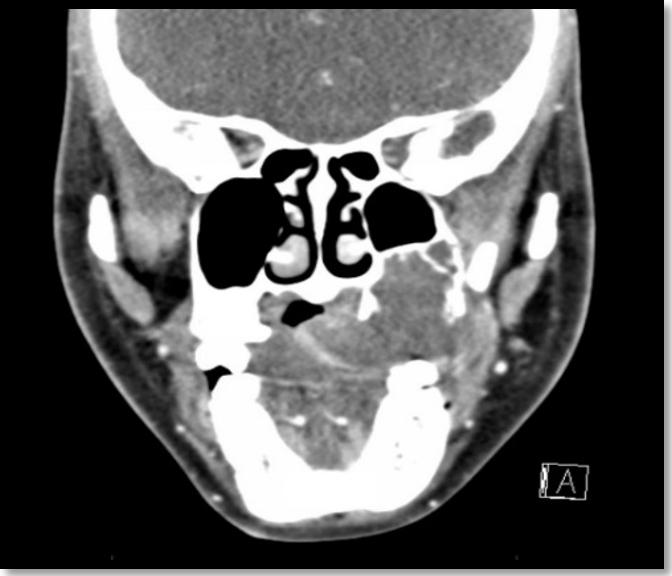

8.OdontogenicMyxoma:CaseReport (Pg.77-86)

MyxomaOdontogénica:ReportedeCaso

EvaChiang,DDS,MPH,LynnSolomon,DDS,MS,ElíasMorón,DDS,MPH,MHL